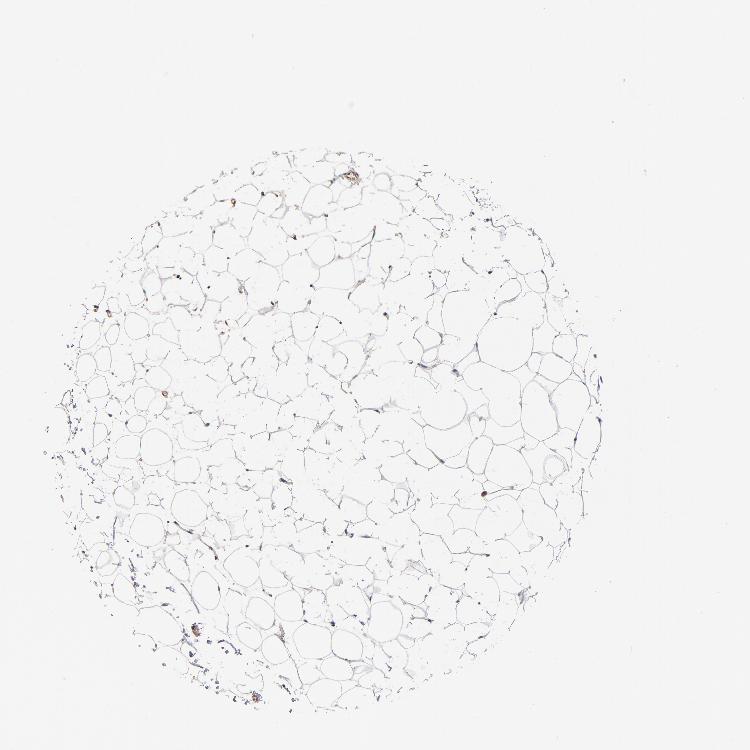

ADIPOSE TISSUE - Antibody stainingi

Antibody staining in the annotated cell types in the current human tissue is reported as not detected, low, medium, or high, based on conventional immunohistochemistry profiling in selected tissues. This score is based on the combination of the staining intensity and fraction of stained cells.

Each image is clickable and will lead to virtual microscopy that enables deeper exploration of all samples and also displays staining intensity scores, fraction scores and subcellular localization as well as patient and tissue information for each sample.

Antibody HPA003910

Adipocytes Not detected